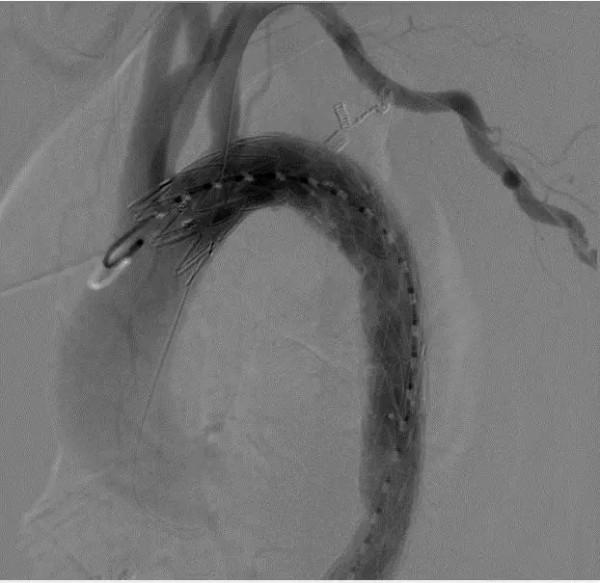

手術中,主任醫師首先經左肱動脈及右股動脈穿刺造影,再次全面評估胸主動脈夾層破口部位及長度,助手姚辰亮主治醫師按照術前測量值將DSA導管機精確調整好角度。醫生首先將主動脈覆膜支架自鞘管取出,依術前的設計在特定的位置進行打孔“開窗”,隨後在姚辰亮和蔡志文醫生的協助下將支架原位重新裝回鞘管內。第二枚主動脈覆膜支架自股動脈穿刺點匯入,於降主動脈正常錨定區釋放支架以封閉第二破口。經導絲交換已“開窗”支架,經過定位、選擇後,將“視窗”與左鎖骨下動脈精準對接。造影顯示弓上三支血管顯影良好,血流速度快,支架近遠端未見內瘻,手術順利結束。

△ 手術後主動脈弓三分支顯影良好,支架準確對位,術後患者體表僅遺留不足1cm的穿刺孔